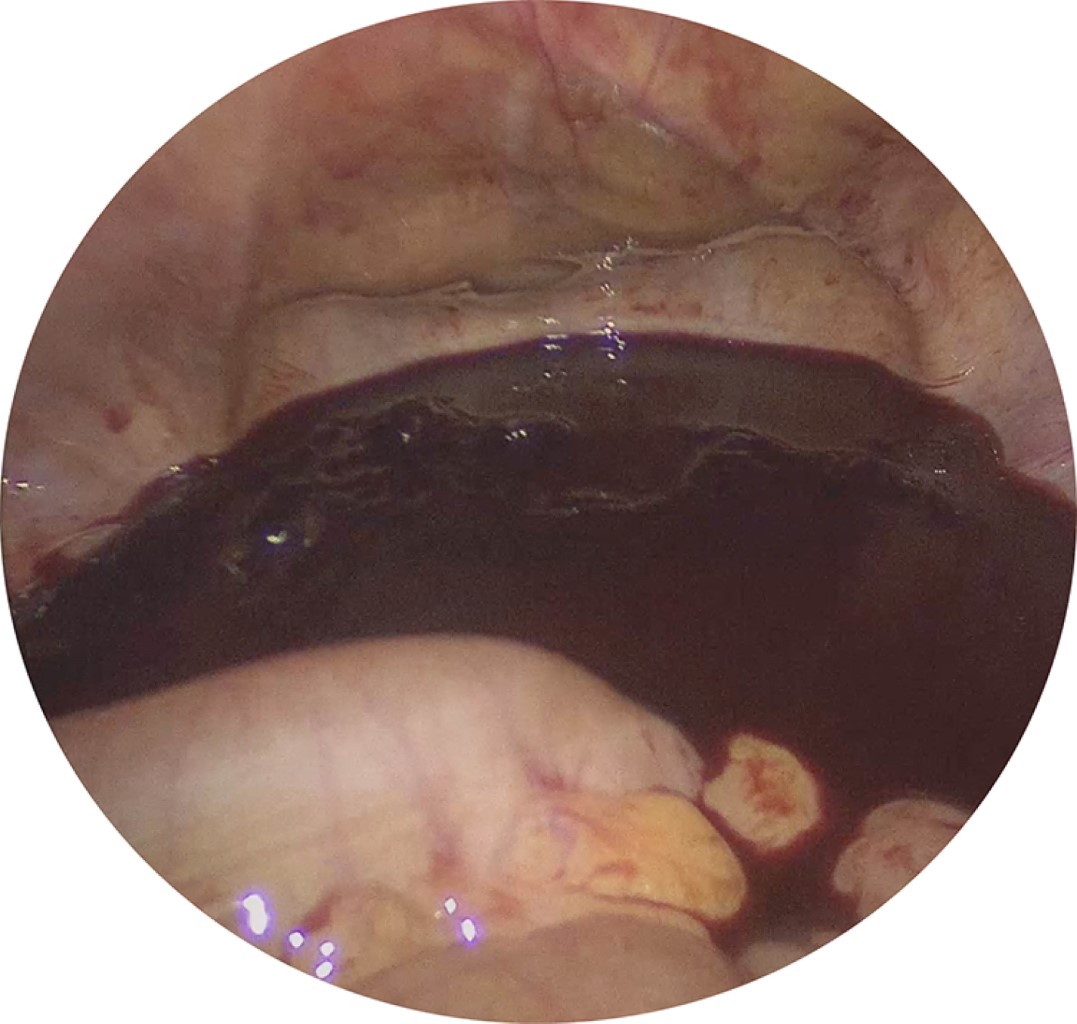

Debido a estos hallazgos, la paciente fue sometida a laparoscopía exploradora en donde se evidenció hemoperitoneo de 2,000 cm3 que fue aspirado (Figura 2) y una lesión de 5 mm de diámetro en la cara anterior del fondo uterino como origen de la hemorragia (Figura 3). Se procedió a realizar cierre hemostático utilizando sutura absorbible 2-0 (Figura 4), la paciente tuvo una evolución favorable, tolerando vía oral de manera temprana, con signos vitales dentro de parámetros normales durante todo su internamiento y sin requerimiento de transfusión de hemoderivados, fue dada de alta del servicio al cumplir 24 horas de estancia intrahospitalaria.

Figura 2